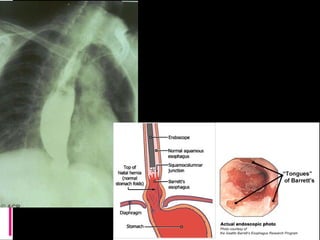

Intestinal involvement

1) esophagus: hypomotility and retrosternal pain,

reflux esophagitis, stricture

Gastrointestinal

 Disordered peristalsis of the lower two thirds of the

esophagus presents as dysphagia

 Impaired function of the lower esophageal

sphincter

 chronic esophageal reflux include erosive

esophagitis with bleeding, Barrett's esophagus,

and lower esophageal stricture